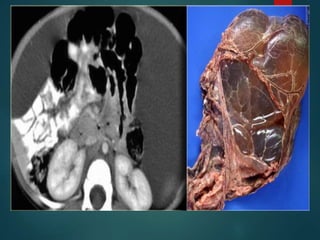

Desmoplastic Small RoundCell Tumor… • Rare malignancy of uncertain origin. • Young men with a mean age of 19 years. • Consider this diagnosis if we see something that looks like peritoneal carcinomatosis in a young man that has no history of a primary malignancy. • It is a very aggressive tumor with a poor prognosis.

• #54 It occurs primarily in young men with a mean age of 19 years.

• #55 THEY BEGIN AS A dominant mass and then multiple masses occur within the peritoneum As this stage it is no different upon imaging to other tumors,however age of the patient provides clue for diagnosis. NHL b the close d/d.